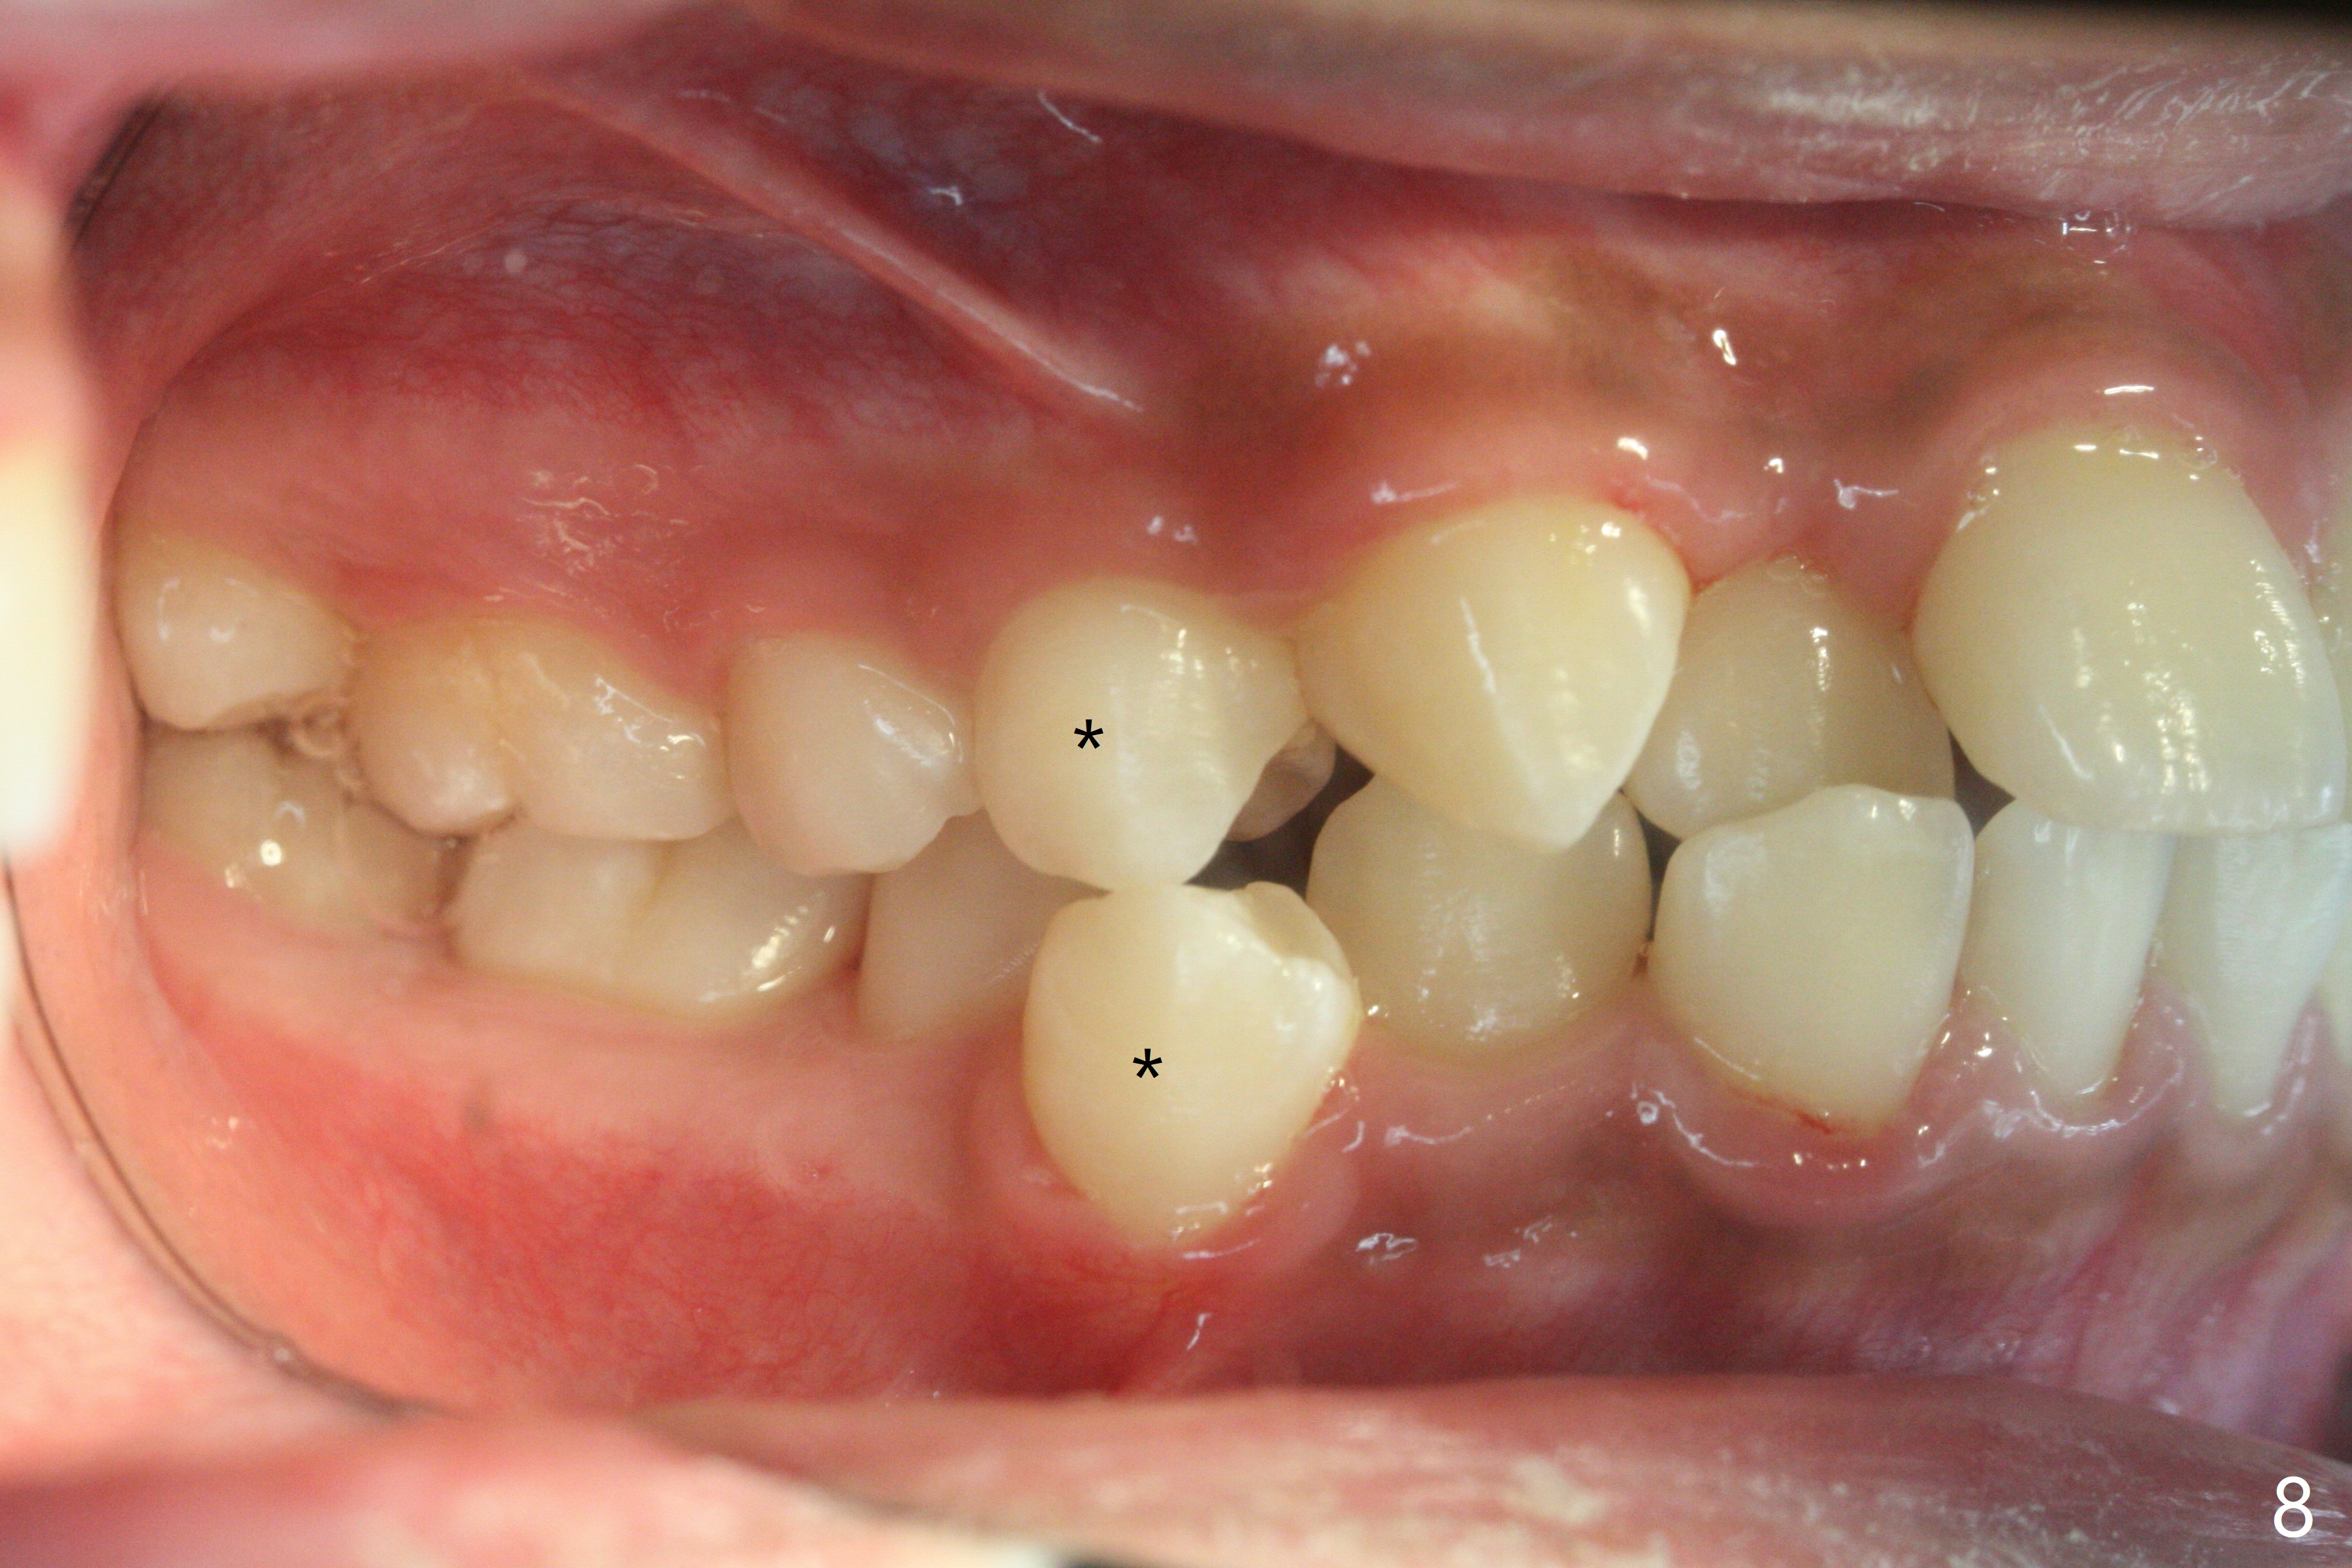

A 13-year-old man has protrusive lips (Fig.1,3,4) with upper midline deviation to the left (Fig.2).  Crowding is severe with LR5 severe lingual inclination (Fig.5,6,10).  To facilitate L6s' uprighting (Fig.10), LR5 and 3 of the 1st bicuspids will be extracted (Fig.6-8 x or *) and molar bands with lingual cleats will be used for the lower.  Cross arch molar retraction will be initiated immediately.  Open coil spring will be placed between UL1 and 3 with the 1st wires to correct the upper midline deviation and to gain the space for UL2.

The patient will return 2 months post extraction.  Shifting is expected to occur next to extraction sites (*) as indicated by arrows in Fig.9,11.  Take photos if it is the case.  Place bracket at UL2 if there is no space issue, but upside down (why?).  The most flexible wire is anticipated.  To establish Class I occlusion when wires are stiffer (18ss), LL5,6 will be mesialized as equally as LL3 distalized, while UL5,6 maintained basically in situ (Fig.11).  How to accomplish?

In fact, automatic shifting is striking.  For example, UR5 lingualization (Fig.12 arrow) makes it easy to insert 12 niti wire.  Distalization of the lower bicuspids and canine is more obvious (Fig.13,14 arrows) than the upper counterparts.  Because of incomplete eruption, it is difficult to band L7s; instead brackets are placed (Fig.15-17).  The purpose of LR one is to facilitate LR6 buccalization (Fig.15,16), whereas LL one to correct rotation of itself (Fig.17).